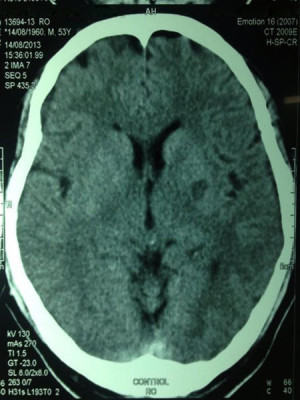

Casos Neuroloquirúrgicos

Envíado por Dr. Ruben Eduardo Amaya Contreras